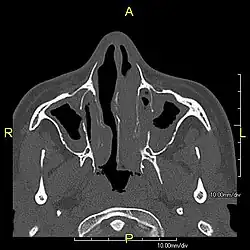

Axial CT image showing chronic sinusitis in an individual with Kartagener syndrome

When accompanied by the combination of situs inversus (reversal of the internal organs), chronic sinusitis, and bronchiectasis, it is known as Kartagener syndrome[3] (only 50% of primary ciliary dyskinesia cases include situs inversus).[11]